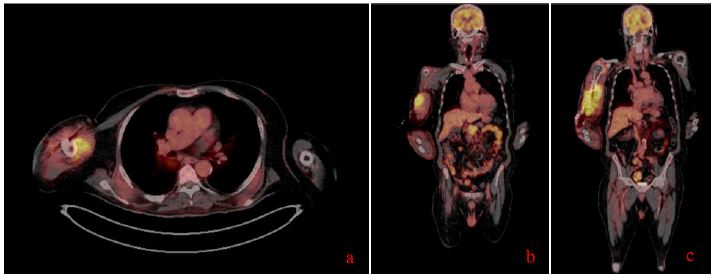

The patient demonstrated a significant clinical improvement following 3 weeks of the initiation of daratumumab and lenalidomide therapy. Serial imaging studies, done in january 2025, showed a marked reduction in the size of both the humeral and pancreatic masses, with complete resolution of the lytic bone lesion and near-total disappearance of the pancreatic mass. These findings were corroborated by clinical evaluation, with the patient reporting resolution of symptoms such as pain and swelling at the site of the previous humeral mass.

Figure 3: (A-C) Different sections of the patient’s follow up PET CT scan (January 2025) showing a complete morpho-metabolic remission of the large intensely hypermetabolic tissue mass in the pancreatic head and complete metabolic remission of the large intensely hypermetabolic skeletal muscle tissue mass in the right arm with humeral involvement, described on the PET scan of September 30, 2024.

As of the latest follow-up, the patient continues to show complete morpho-metabolic remission, with no new hypermetabolic lesions identified on PET-CT since January 2025.